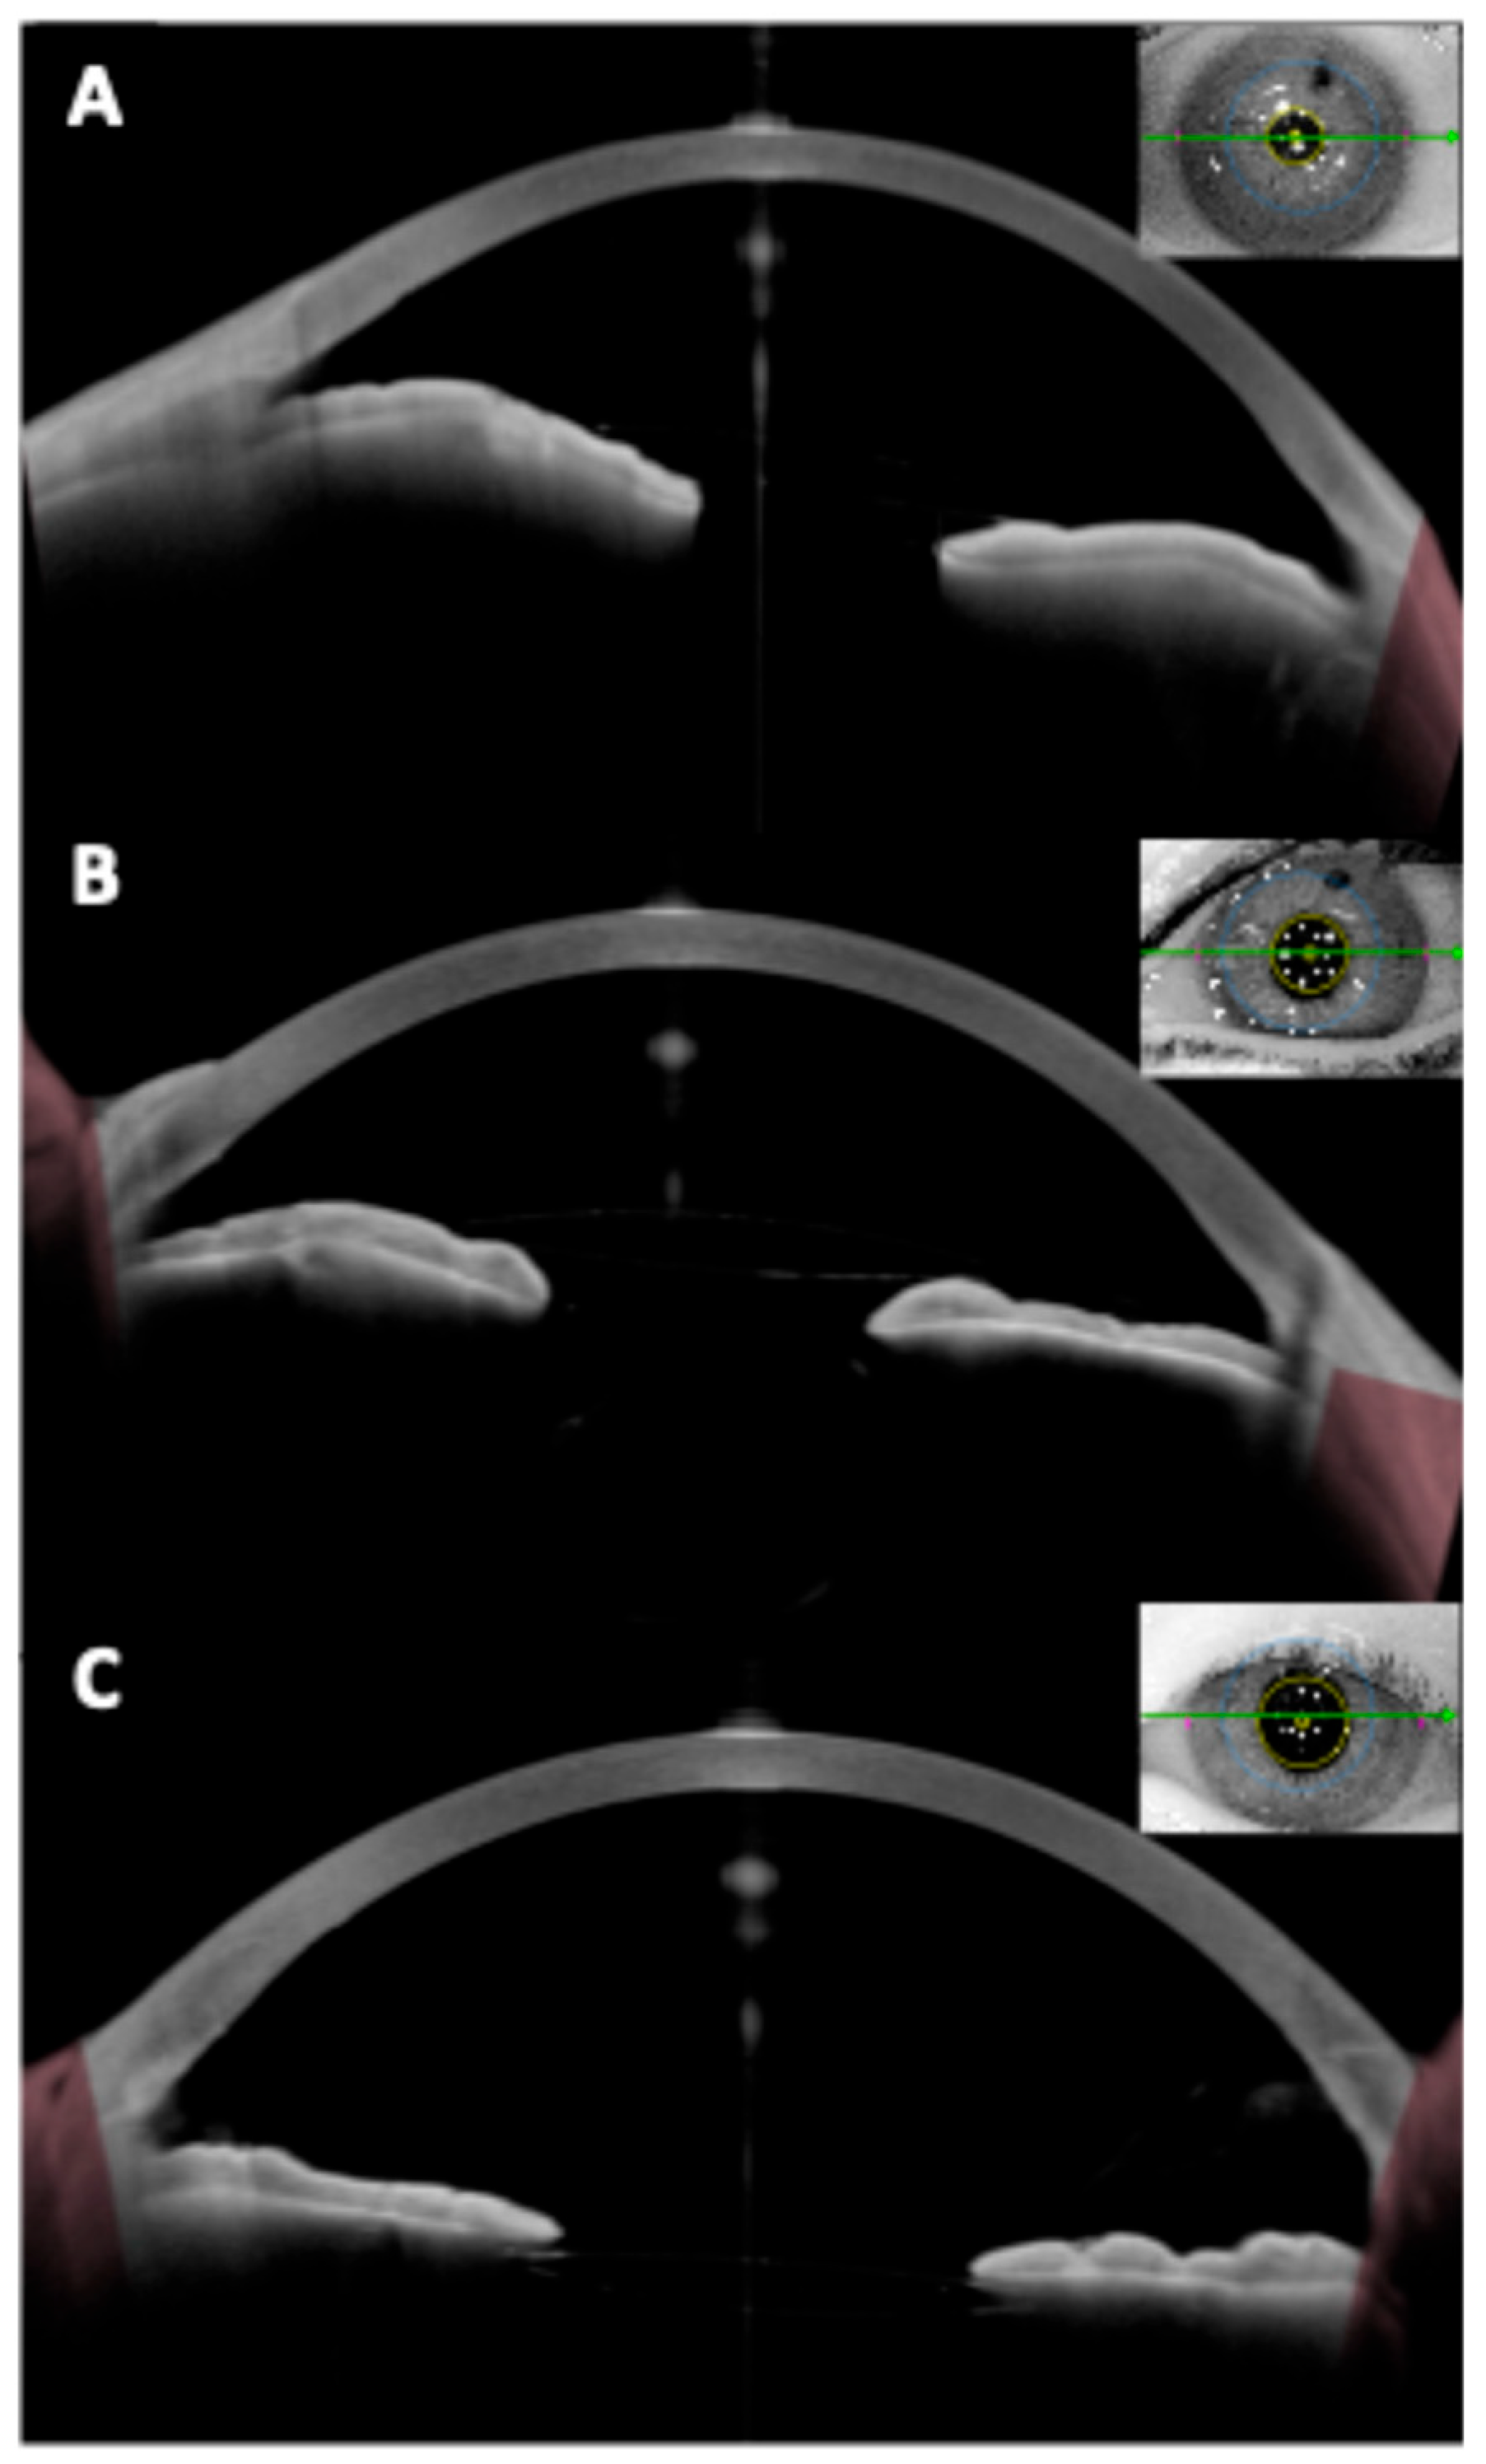

3. OCT for Secondary (Pseudophakic) IOL Fixation Techniques

Beyond phakic refractive lenses, OCT has significant utility in secondary IOL fixations—cases where an intraocular lens is implanted in an eye without capsular support. This includes scleral-fixated IOLs (both sutured and sutureless Yamane-type), Carlevale lenses (a one-piece lens with T-shaped scleral anchoring plugs), iris-claw lenses used for aphakia, and other innovative techniques [46,47,48,49,50] (Figure 6 and Figure 7). These scenarios present unique imaging challenges, as the IOL is often located in the posterior chamber or at the iris plane, and the supports (haptics, flanges, or sutures) are not within the visible pupil.

Anterior segment OCT (especially swept-source) and even posterior segment OCT (for certain views) have been employed to evaluate the positioning and outcomes of these secondary IOLs (Table 3). OCT assures proper lens positioning (centration/tilt), verifies fixation integrity (flange/plug location), and detects any secondary anatomical changes (iris configuration, macular edema) that might require intervention. This has translated into improved patient outcomes. For example, the knowledge that Yamane and sutured fixations yield comparable tilt means surgeons can choose either technique based on other factors [45]. The ability to detect issues like reverse pupillary block (RPB) early via OCT has led to modifications in technique (such as performing an iridotomy at the time of Carlevale lens insertion) [51]. As new secondary lens designs emerge, OCT will likewise be critical in evaluating their safety.

3.2. Tilt and Decentration in Scleral-Fixated IOLs

Tilt and decentration are particularly pertinent for secondary IOLs because the lack of capsular bag support can lead to more IOL movement. Several studies using OCT have quantified this. Cui et al. [45] performed a prospective comparison of Yamane flanged intrascleral fixation and traditional sutured scleral fixation, measuring IOL tilt and decentration at 3 months with CASIA OCT. They found no significant difference between the two methods: both had mean tilt ~2–3° horizontally and ~3–4° vertically, and mean decentration around 0.3 mm, with no statistically significant disparities. These values are only slightly above in-the-bag IOL norms, indicating that with proper technique, secondary fixations can achieve near-normal alignment. Similarly, Do et al. [54] found no differences using CASIA2 OCT.

Earlier studies using Scheimpflug photography were less accurate and had conflicting findings. Sül et al. [55] reported with Scheimpflug that flanged IOLs had on average ~1° less tilt than sutured. OCT being a direct measure, it most likely provides the more reliable answer: modern flanged techniques do not inherently introduce more tilt/decentration than suture fixations.

Nonetheless, individual cases can have significant tilt, and OCT can identify those outliers. For example, if a haptic is not well fixated in the scleral tunnel, the IOL might tilt towards that side. A visually significant cutoff is often ~5° tilt [53]. OCT can directly confirm if an eye exceeds that, and one may then consider re-fixating the lens. Decentration in scleral-fixated lenses tends to be directional: one study found most sutured IOLs decentered infero-nasally (due to loop slack), whereas flanged IOLs were more randomly distributed [45].

CASIA OCT polar plots may be helpful in visualizing this decentration pattern. Knowing the magnitude and direction of malposition via OCT is extremely helpful if surgical adjustment is planned—the surgeon knows which scleral fixation point to tighten or whether the IOL might need to be completely refixated [6].

Figure 6. (A,B) Images showing an anterior iris-fixated intraocular lens (Artisan) implanted in an aphakic eye, with good optic centration. (C) Image of a posterior (retroiridian) iris-fixated intraocular lens, also implanted in an aphakic eye, demonstrating proper centration.

Figure 7. Anterior segment optical coherence tomography images showing a well-positioned Carlevale sutureless scleral-fixated intraocular lens with (A) vertical and (B) horizontal cross-sectional scans demonstrating central optic positioning, slight tilt, and adequate distance from the corneal endothelium and iris plane. (C,D) Images show both haptics of the Carlevale lens anchored within intrascleral tunnels approximately 1.5–2.0 mm posterior to the limbus.